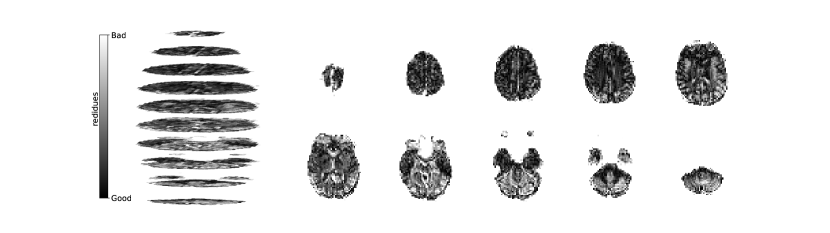

Figure 2 illustrates the distribution of residues (observed vs. estimated differences) on the fMRI volumes for the NODDI dataset. Clearly, by visual inspection, (iv) model has the darker and biggest area of shaded regions, which implies a better coverage across the brain regions and better synthesis quality. Models with topographical attention, (ii) and (iv), corresponding to Figures 2(b) and 2(d), respectively, significantly improve the synthesis, as shown by the darker and bigger areas against (i) and (iii) depicted in Figures 2(a) and 2(c), respectively. Particularly, we notice that models (i) and (iii) report difficulty in the retrieval of haemodynamical activity located in occipital and parietal lobes.

To better address which regions our baselines had more difficulty retrieving, the normalized residues were computed and are illustrated in Figure 3. Baselines – corresponding to models (i) and (ii), shown in Figures 3(a) and 3(b) respectively, which correspondingly implement a linear projection in the latent space and topographical attention –, have difficulty retrieving the prefrontal, occipital and parietal lobes, as the shade tends to a lighter grey in that region. Model (iv), shown in Figure 3(d), does not show a noticeable region with a lighter tone of grey, which implies no evident difficulty in retrieving haemodynamical activity across the different brain regions.